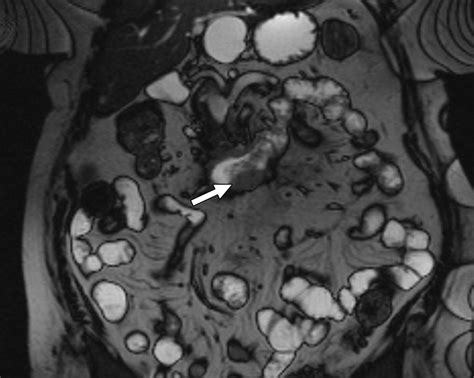

• CT Enterography: A type of CT scan that uses a contrast agent to visualize the small intestine in detail.

• MRI Enterography: Similar to CT enterography, but uses magnetic resonance imaging instead of X-rays.